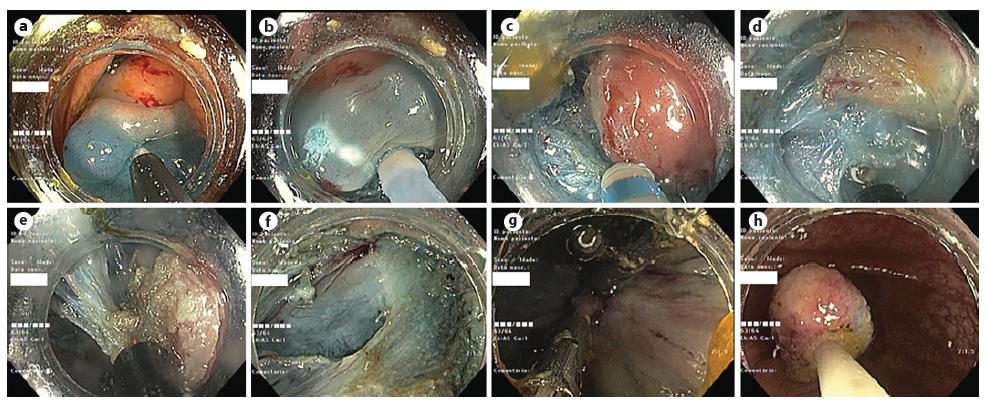

Endoscopic submucosal dissection (ESD) was pro-posed. The endoscopist had extensive experience in colorectal ESD. A glycerol solution with indigo carmine and adrenaline (1:50,000) was injected (Fig. 2a). Mucosal incision was performed (Fig. 2b), followed by submucosal endoscopic dissection using DualKnife JTM (Olympus, Tokyo, Japan) and IT Knife nanoTM (Olympus, Tokyo, Japan), with dry-cut current effect 2.5 and swift coagulation current effect 3 achieving total excision of the lesion at the end of the procedure (Fig. 2c-e). The scar was closed with Resolution 360TM ULTRA clips (Boston Scientific, Boston, USA) (Fig. 2f, g). The lesion was retrieved en bloc (Fig. 2h). No adverse events were observed.

Fig. 2. Endoscopic submucosal dissection. a Submucosal injection. b Mucosal incision. c-e Submucosal dissection. f Dissection scar. g The scar was closed with clips. h En bloc lesion retrieval.